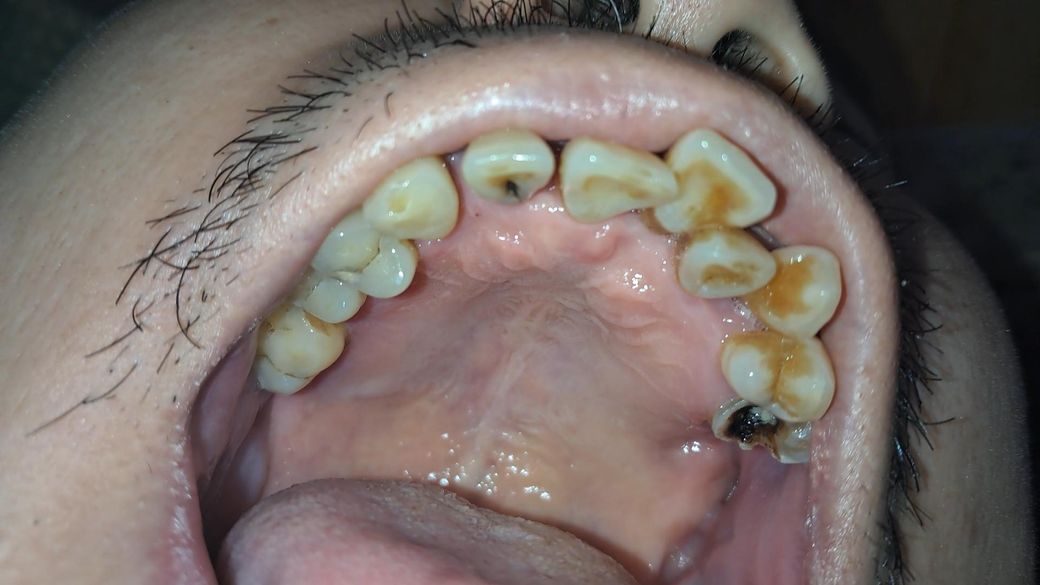

• 2번 째 사진

해당 부분을 구강암으로 의심해볼 수는 없고 크기가 계속 커지거나 하면 검사 받으러가심이 좋습니다.

구강암은 아니고 잇몸에상처가 생긴거 같으니 크게 걱정은 안하셔도 될것같습니다. 자극만 가지 않도록 해주세요.

1. 악성종양의 양상 아닙니다

2. 그 외 치료해야 할 충치 많고 스케일링 한번 하셔야 겠습니다...